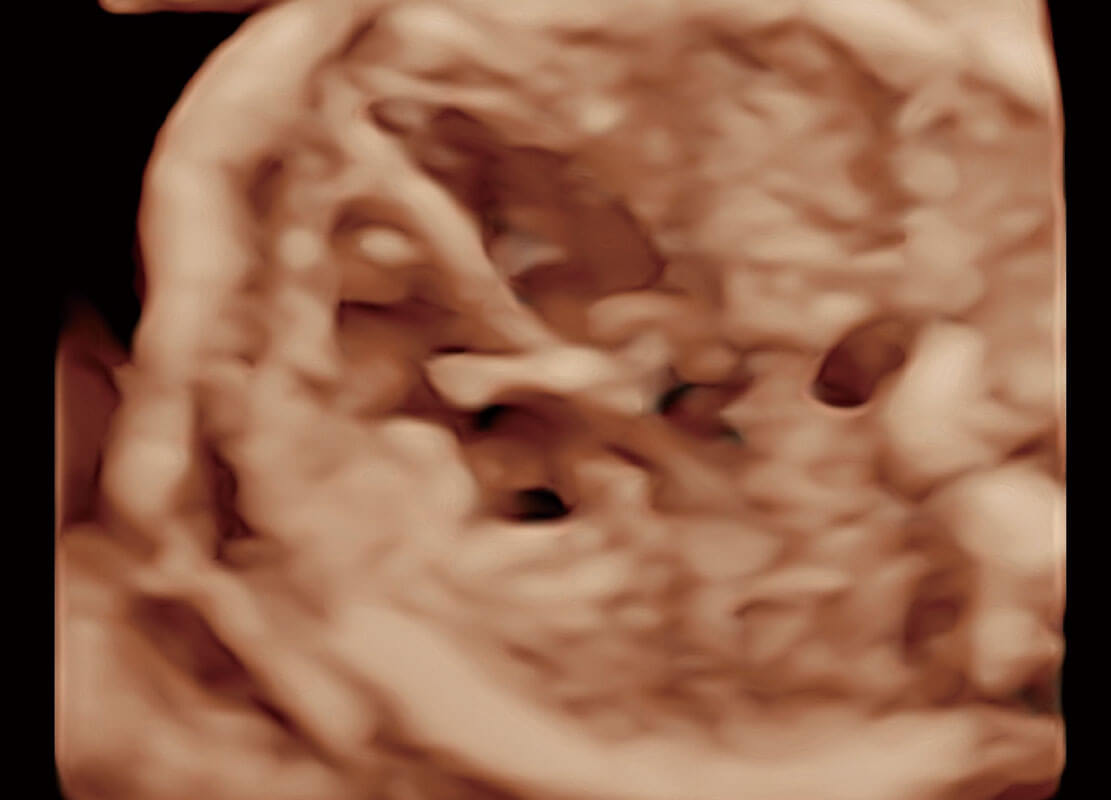

P60搭载一系列胎儿心脏成像技术,实现精细的胎儿心脏评估。

四腔切面

四腔心血流

右室双出口

胎心容积成像